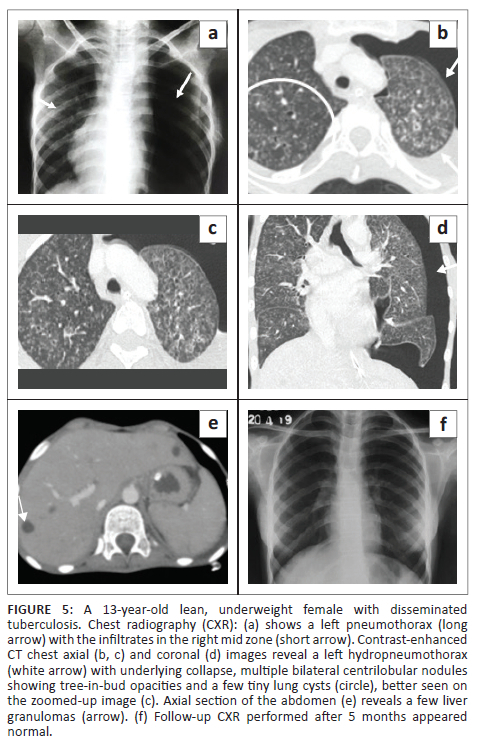

A 13-year-old emaciated, underweight girl presented with a cough for 12 days and projectile vomiting, associated with altered sensorium, blurring of vision and double vision over the preceding 4 days. There was a history of low-grade fever for 1 month associated with decreased appetite, weight loss and night sweats. The patient also had a positive contact history for pulmonary TB from her grandmother. Non-contrast CT brain at another facility (not shown) revealed communicating hydrocephalus and a hypodense fluid collection in the prevertebral space at the C2-C3 vertebral level, suggestive of a prevertebral abscess. Clinical and cerebrospinal fluid (CSF) findings suggested the diagnosis of tuberculous meningitis and the child was started on ATT. During her hospital stay, she developed sudden respiratory distress. The CXR (Figure 5) revealed a left pneumothorax with a few infiltrates in the right mid zone. An intercostal drainage (ICD) tube was subsequently placed. Sputum GeneXpert detected MTB. A CT of the chest (Figure 5) demonstrated a left hydropneumothorax with underlying collapse, multiple centrilobular nodules and a TIB pattern in both lungs, a few tiny cysts in both upper lobes, patchy consolidation in the right lower lobe, mediastinal lymph nodes with calcification, and hepatosplenomegaly with multiple liver and splenic granulomas. The patient improved on ATT and follow-up CXR (Figure 5) after 5 months revealed resolution of the radiographic findings.

Most patients with tuberculosis who develop lung cysts have extensive bilateral infiltrative and exudative disease as a result of the pneumonic process.1,4,7 All the described cases had disseminated TB (with involvement of two or more noncontiguous sites), along with diffuse, bilateral lung involvement. These cystic lung lesions are often associated with centrilobular nodules and branching opacities in surrounding areas.2,3,6 Antibiotics were administered in all five cases, and none showed superadded bacterial infection. Three cases revealed numerous nodules, GGOs and consolidations. In Case 2, two CT studies were performed 2 months apart, which demonstrated a reduction in the lung nodules on treatment, with a corresponding increase in the number of cysts. Two cases showed predominantly cystic changes, with only a few nodules. One of these (Case 5) had received 5 months of ATT for MDR TB. In the presented cases, the cystic lesions developed during isoniazid treatment, rather than before or after treatment. This is in contrast to previous literature that describes certain instances of patients developing cystic lung lesions after isoniazid treatment.7

Tuberculous cysts are prone to rupture, leading to the development of recurrent pneumothoraces or pneumomediastinum.1,2,7,9 Pneumothorax was seen in four of the cases, likely as a result of cyst rupture. However, in Case 1, both cyst rupture and additional mechanical ventilation possibly played a role in the development of pulmonary interstitial emphysema and pneumomediastinum, which is difficult to differentiate radiologically.

According to previous literature, the evolution of cysts in tuberculosis may show varying severity, extent and an unpredictable outcome during the course of the disease. In some cases, cysts are reversible, while in others, the cysts remain static without progression and may persist on follow-up imaging.1,2,3,7 In this study, the cystic lesions were not evident on follow-up CXR in two cases, while one case (Case 5) showed persistent linear and fibrotic opacities on follow-up.